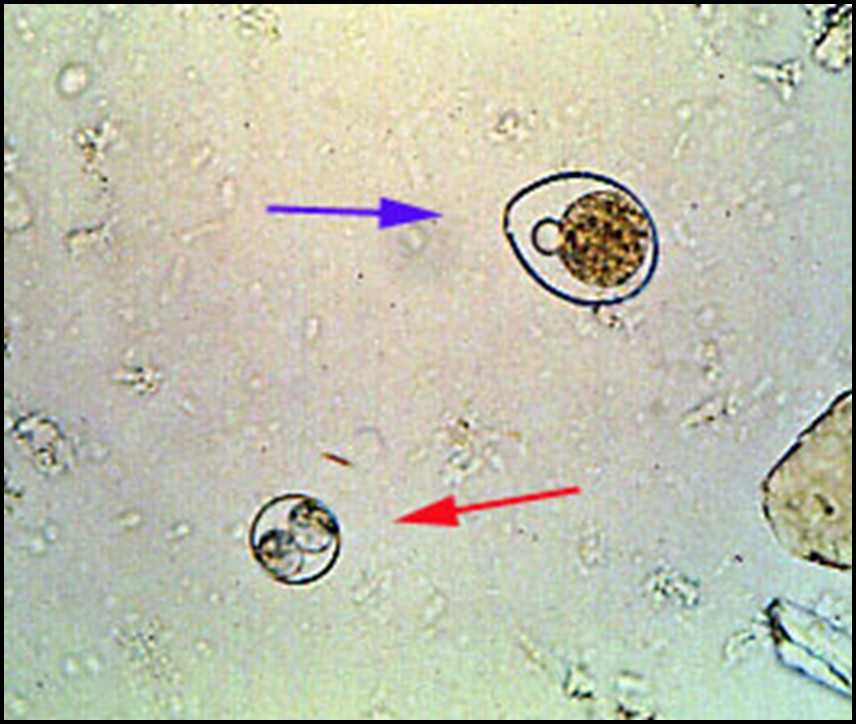

Микрофотографии яиц гельминтов Toxocara canis

Раздел: Фотоэссе